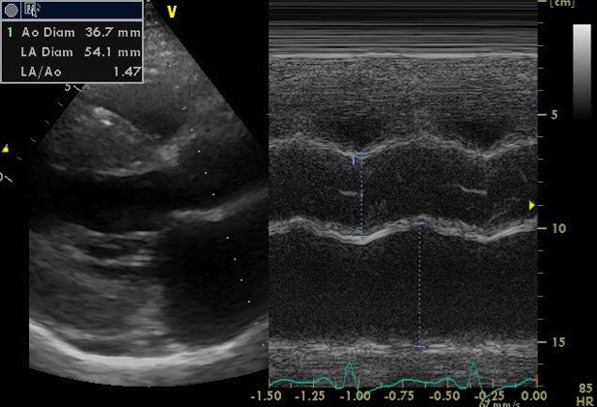

心エコー検査では、弁機能に異常なく、心嚢液の貯留はない。左房径(64mm)と左室径(60mm)は著明に拡張、左室は瀰漫性に壁運動の低下(EF=20%)。左室壁は中隔厚(18mm )、左室後壁厚(21mm)と共に肥厚しており、長年の左室圧負荷に加え、左室の収縮不全を認めることから、高血圧性心疾患に加え何らかの心筋疾患の可能性も否定できない。

心エコー画像1